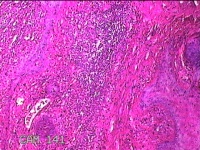

右侧头皮息肉

性别

男

年龄

46岁

临床诊断

一般病史

发现右侧头皮息肉2年余。

大体所见

带皮肤组织2x1.2x0.8cm一块,表面光滑,切面灰白粉红色,质中。

图1